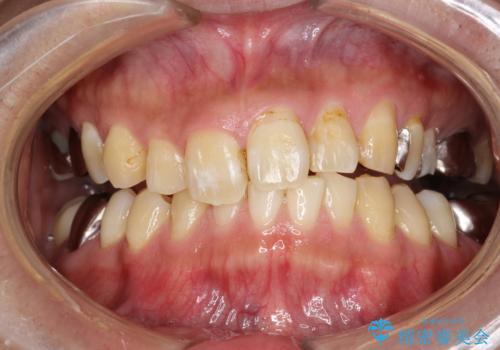

PMTCで歯の着色落とし

- 歯の着色・汚れが気になるとのことでクリーニンング希望とのことでした。PMTC30分コースを行いました。

プラーク(細菌の塊)や歯石がたまると歯の表面はザラつきいてきます。そのザラつきは歯周病や虫歯菌の棲家となります。そのまま放置すると、歯肉が腫れてきたり、歯肉から出血したり、口臭が強くでたりします。とくに歯肉の境目は、歯磨きで汚れを除去することが難しく、プラーク(細菌の塊)や歯石が溜まりやすい場所です。